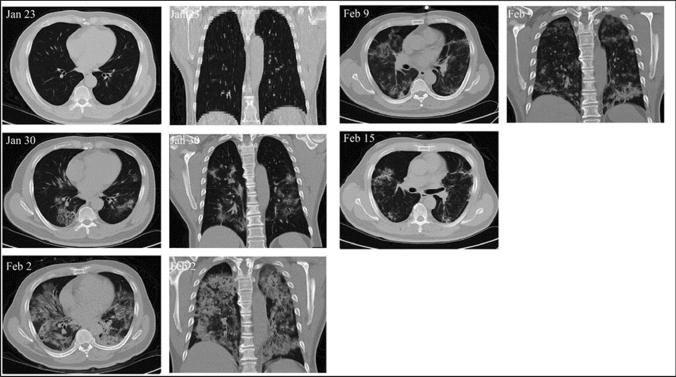

COVID-19 has severely devastated many lives across the globe. It has been speculated that stem cell-based therapy for COVID-19 treatment could be able to subsidize the effects. In preclinical and clinical studies, stem cell-based therapy has successfully eliminated inflammatory cytokines in ALI, ARDS, and COVID-19. Clinical trials have produced a variety of promising results for validating stem cell therapy in COVID-19 patients. For instance, exosome-based therapy (ExoFlow) showed an 87% survival status, and MSC-based therapy (Mesoblast) achieved an 83% survival rate in moderate to severe COVID-19 patients. This review debates the advantages of cell-free therapy, i.e., stem cell-derived exosome-based therapies, over stem cell-based therapy. This review aims to question whether the immunomodulatory effect of stem cells differs based on their origin and also tries to find possible answers for the best stem cells for treating SARS-CoV-2 infection. The role of stem cells and their extracellular vesicles in the upregulation of regulatory immune cells, growth factors (EGF, FGF, VEGF), and anti-inflammatory cytokines (IL-6, INF-α, galectin-1, notch-1, PDL-1) that promote the tissue regeneration at the injured site. The right side of the image depicts the downregulation of inflammation-inducing immune cells, pro-inflammatory cytokines, and chemokines that could also enhance COVID-19 therapy.

新型冠状病毒肺炎(COVID-19)在全球范围内严重影响了许多人的生活。有人推测,基于干细胞的治疗方法可能有助于缓解 COVID-19 的影响。在临床前和临床研究中,基于干细胞的治疗方法已成功消除了急性肺损伤(ALI)、急性呼吸窘迫综合征(ARDS)和 COVID-19 中的炎症细胞因子。临床试验为验证 COVID-19 患者的干细胞治疗提供了多种有前途的结果。例如,基于外泌体的治疗(ExoFlow)显示出 87%的存活状态,基于间充质干细胞的治疗(Mesoblast)在中度至重度 COVID-19 患者中达到 83%的存活率。本综述讨论了无细胞治疗(即基于干细胞衍生的外泌体治疗)优于基于干细胞的治疗的优势。本综述旨在质疑干细胞的免疫调节作用是否因其起源而异,并尝试为治疗 SARS-CoV-2 感染的最佳干细胞寻找可能的答案。干细胞及其细胞外囊泡在调节性免疫细胞、生长因子(EGF、FGF、VEGF)和抗炎细胞因子(IL-6、INF-α、半乳糖凝集素-1、 Notch-1、PDL-1)的上调中的作用,这些因子促进受损部位的组织再生。图像的右侧描述了炎症诱导免疫细胞、促炎细胞因子和趋化因子的下调,这也可能增强 COVID-19 的治疗效果。